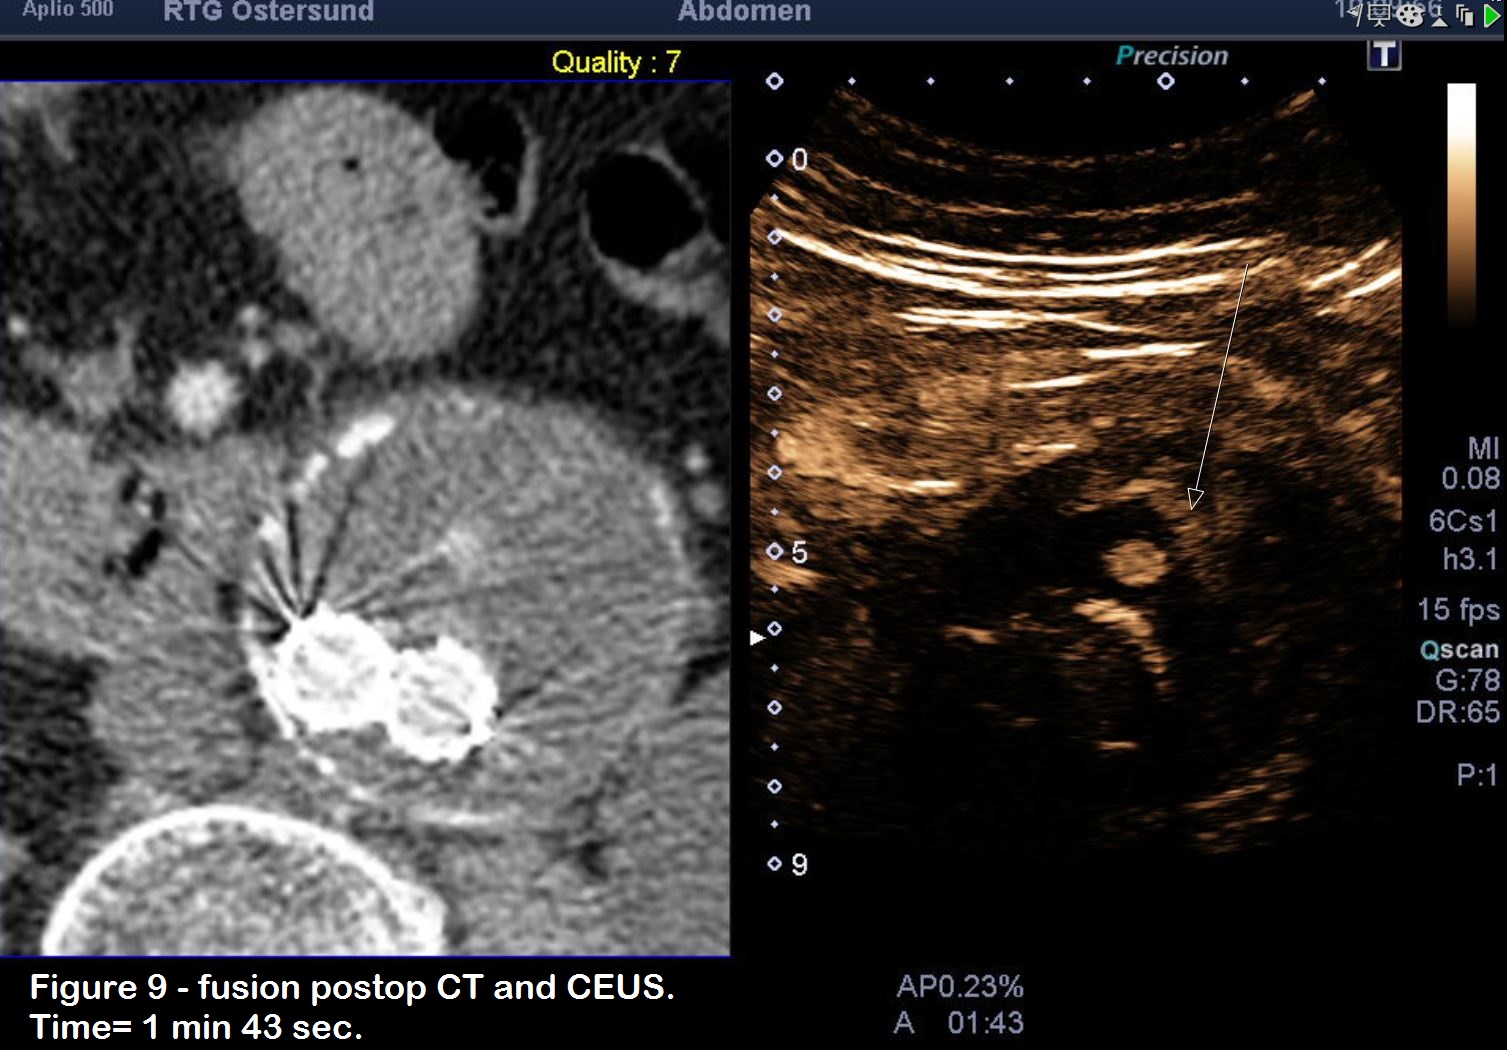

Figure 9: Delayed images shows “pooling” of US contrast (Sonovue) in the ventral portion of the aneurysm sac, probably due to both endoleakages.